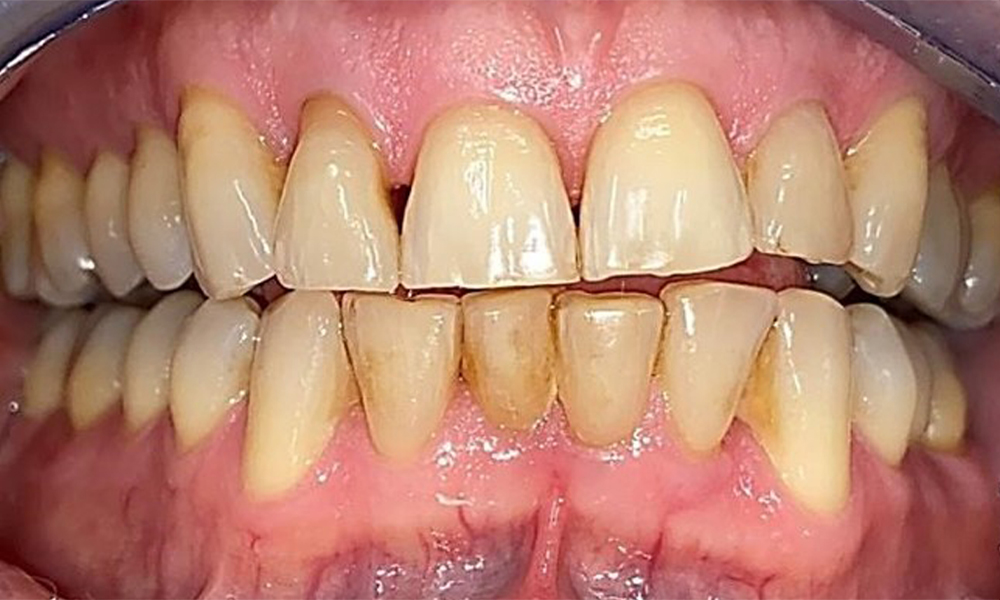

Пациентът има пълно съзъбие с 28 зъба, което включва амалгамни и композитни пломби в областта на моларите и премоларите. На зъб 14 има видима клинична маргинална празнина. Зъб 27 има адекватна златна инкрустация. Налице са и генерализирани атриции и абразии. (фиг. 2, фиг. 3, фиг. 4, фиг. 5, фиг. 6)

Пациентът е с пародонтит II стадий, степен В (5). Клиничните дълбочини на сондиране от 1 до 3 mm са във физиологичния диапазон. Локализирани дълбочини на сондиране от 5 mm са наблюдавани медиопалатинално на 17 и 27. Налице са генерализирани рецесии от 1 до 3 mm с частична загуба на интердентални папили (фиг. 2, фиг. 3, фиг. 4)